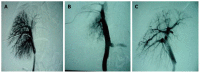

Methods: Twenty-one healthy Guizhou miniature pigs were randomly divided into three experimental groups and three control groups. The pigs in the three experimental groups were subjected to hepatic arterial perfusion with 7, 12 and 17 mL of 80% alcohol, respectively, while those in the three control groups underwent hepatic arterial perfusion with 7, 12 and 17 mL of saline, respectively. Hepatic arteriography and direct portal phlebography were performed on all animals before and after perfusion, and the portal venous pressure and diameter were measured before perfusion, immediately after perfusion, and at 2, 4 and 6 wk after perfusion. The following procedures were performed at different time points: routine blood sampling, blood biochemistry, blood coagulation and blood ammonia tests before surgery, and at 2, 4 and 6 wk after surgery; hepatic biopsy before surgery, within 6 h after surgery, and at 1, 2, 3, 4 and 5 wk after surgery; abdominal enhanced computed tomography examination before surgery and at 6 wk after surgery; autopsy and multi-point sampling of various liver lobes for histological examination at 6 wk after surgery.

Results: In experimental group 1, different degrees of hepatic fibrosis were observed, and one pig developed hepatic cirrhosis. In experimental group 2, there were cases of hepatic cirrhosis, different degrees of increased portal venous pressure, and intrahepatic portal venous bypass, but neither extrahepatic portal-systemic bypass circulation nor death occurred. In experimental group 3, two animals died and three animals developed hepatic cirrhosis, and different degrees of increased portal venous pressure and intrahepatic portal venous bypass were also observed, but there was no extrahepatic portal-systemic bypass circulation.